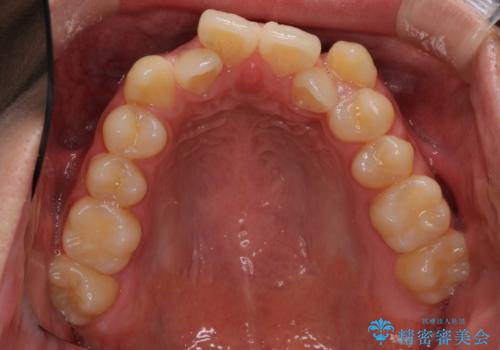

- 上下の八重歯や乱杭歯を気にして来院され患者様です。

スペースを確保するため、上下左右の小臼歯を抜歯し、ワイヤー装置に矯正することとしました。

奥歯の咬み合わせの左右差が大きかったため、変則的な抜歯矯正を行いました。

治療期間はやや長期化しましたが、満足のいく歯並びとなりました。